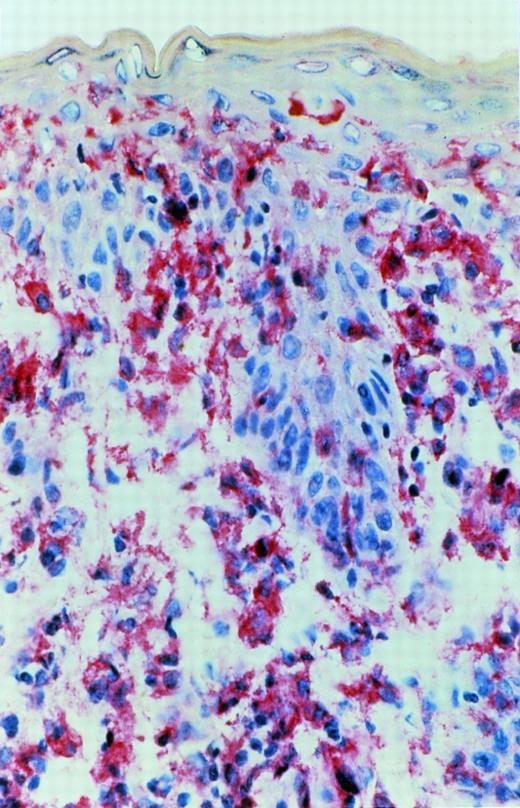

Immunoreactivity for IL-15 was detected in epidermal cells, especially in the basal layer of the epidermis, in cells with a dendritic morphology in the dermis and in mononuclear cells. This immunoreactivity could be blocked by exogenous recombinant IL-15. In early CTCL lesions (patches) (n = 5), immunoreactivity was strongest in the junction zone between epidermis and dermis where the lymphocytic infiltrates show their highest densities (Fig 7). In advanced lesions (plaques) (n = 5), immunoreactivity was also detected in deeper parts of the dermis in areas heavily infiltrated by mononuclear cells (Fig 8).

A more advanced CTCL lesion (plaque stage): immunoreactivity for IL-15 after APAAP staining was detected in the junctional area and in deeper parts of the dermis heavily infiltrated by mononuclear cells.

Our immunohistological investigations detected IL-15 immunoreactivity restricted to the junction zone between epidermis and dermis in early lesions of MF (Fig 7). In this area keratinocytes, dermal dendritic cells, or lymphocytes could produce this cytokine. Because the area of IL-15 production includes the area where CTCL cells preferentially home, we propose that IL-15 is a paracrine/autocrine growth or viability factor and/or a chemotactic factor in early CTCL lesions.

In advanced lesions (plaques), IL-15 immunoreactivity was also detected in deeper parts of the dermis in areas heavily infiltrated by mononuclear cells (Fig 8). This can confirm our mRNA results, indicating that the dominant T-cell clone can produce the cytokine itself. It is possible that autocrine IL-15 production increases during tumor progression and that CTCL cells therefore lose their dependency on the cutaneous microenvironment.